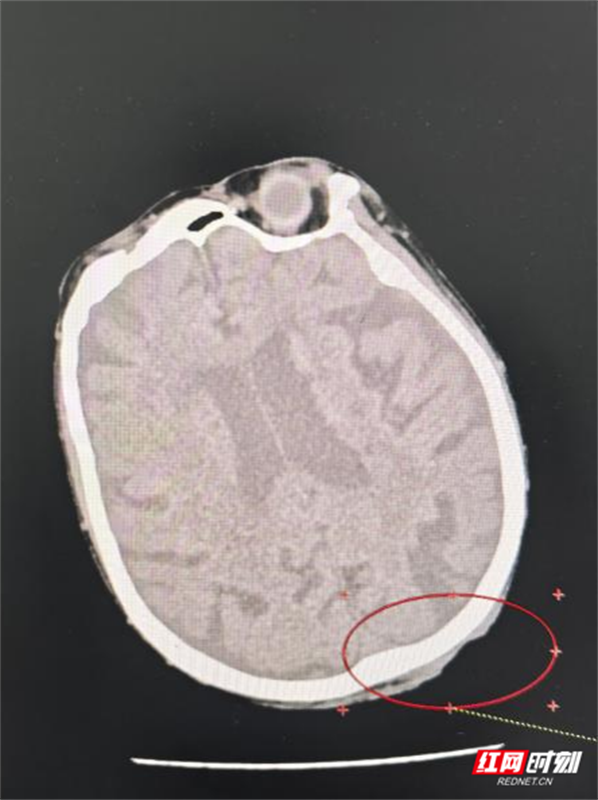

医生为谭奶奶进行了头部MRI等详细检查后,确诊她患“头皮恶性肿瘤鳞癌Ⅲ期”。这一结果让她和家人的心情跌落谷底——在他们看来,肿瘤本身就是难以治愈的疾病,更何况高龄老人还伴有多种基础疾病。

皮肤癌是常见的恶性肿瘤,病理类型以基底细胞癌和鳞状细胞癌为主。其中,鳞状细胞癌的恶性程度相对较高,生长更快,也更容易发生局部侵袭和淋巴结转移。虽然手术切除是首选且主要的根治方式,但在临床上面临诸多实际情况:例如肿瘤生长在鼻、眼、耳等面部关键部位,手术可能严重影响外观与功能;患者年事已高或合并多种基础疾病,无法耐受麻醉与手术;以及部分局部晚期病灶已失去最佳手术时机。

肿瘤血液科副主任黄华深知,对于这样的高龄患者,治疗不仅是技术活,更是“心术”。他与患者和家属充分沟通,用通俗易懂的语言介绍了现代放射治疗方案。这是一种通过三维精准定位技术,再利用高能射线精准靶向肿瘤区域,从而最大限度地保护周围正常组织,把握“控制肿瘤”与“保全生活质量”之间的平衡,这番话大大缓解了谭奶奶和家属原先对“化疗”等治疗的误解与恐惧。

肿瘤放射治疗团队为患者制定了详细、个体化的放疗治疗计划。经过40余的治疗,谭奶奶的疼痛日渐减轻,溃烂面逐渐缩小、愈合。更让她高兴的是整个治疗过程,没有出现呕吐和其他一些不良反应,食欲也没受太大影响,脸上也出现了往日的笑容。